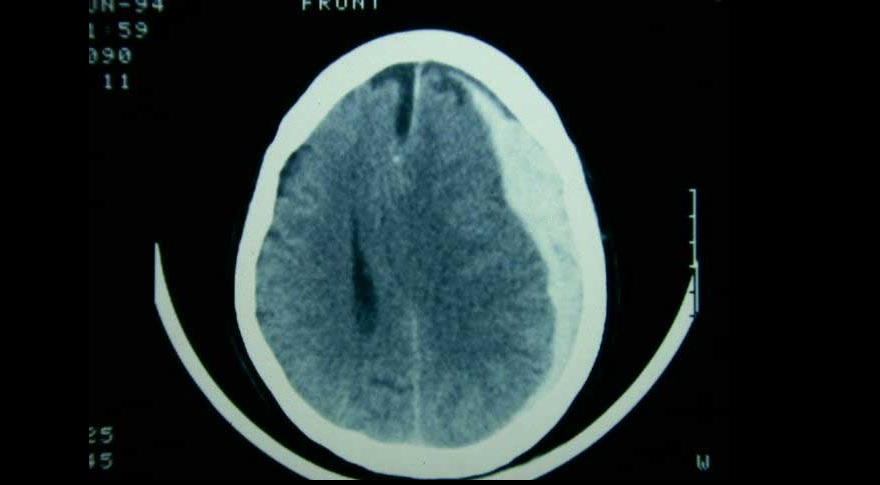

Evacuación inicial o tratamiento conservador en el hematoma subdural agudo

09 mayo 2022

El tratamiento de pacientes con hematoma subdural agudo difiere según el centro de tratamiento, debido a la variación en el abordaje preferido. Una estrategia de tratamiento que prefirió un enfoque agresivo de evacuación quirúrgica aguda sobre el tratamiento conservador inicial no se asoció con un mejor resultado funcional. The Lancet Neurology, 5 de mayo de 2022.